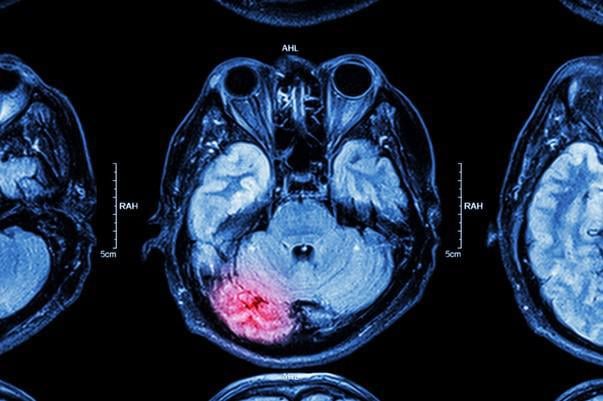

irm de lésion cérébrale cérébrale